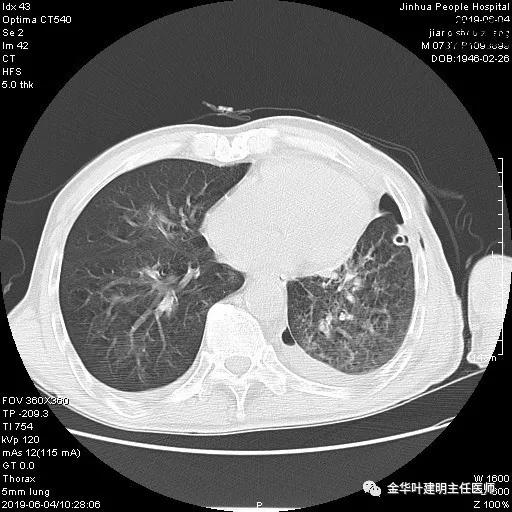

6.4上午:24小时引流出血性乳糜液1800毫升。是否再次手术进行右进胸胸导管结扎,抑或继续保守治疗非常纠结!压力非常大!!多方讨论会诊无法取得一致意见,但一般认为,引流量在1000毫升以上宜积极手术。情况与浙二医院范军强教授联系,请求指导,范教授认为左侧肺手术,损伤胸导管主干的机会较小,多数可保守治疗而愈。在他们的病例中,也有结扎胸导管后引流量仍无减少,效果并不能完全保证。建议可以考虑胸管夹管观察(因为淋巴管压力低,予以适当的压力,漏出量可能会明显减少),同时继续禁食,并静脉营养支持,引流管口可能会有渗液,注意更换敷料。与家属充分沟通后决定试夹管;这天血色素9.0 g/L;胸部CT复查示: